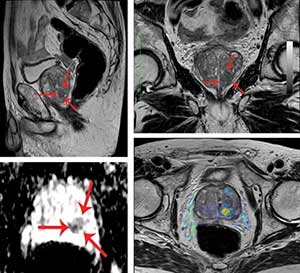

Η πολυπαραμετρική μαγνητική τομογραφία (multiparametric magnetic resonance image, mpΜRI) του προστάτη με έναν μαγνητικό τομογράφο στα 3 Tesla αποτελεί μια σημαντική εξέταση για τη διάγνωση, σταδιοποίηση και επιλογή της καταλληλότερης θεραπείας για τον καρκίνο του προστάτη. Συνδυάζει ειδικές τεχνικές με ανατομικές εικόνες υψηλής ευκρίνειας με αποτέλεσμα τη σημαντική αύξηση της ακρίβειας στην ανίχνευση του καρκίνου. Αποτελεί σημαντικό εργαλείο στην ανάδειξη και τον χαρακτηρισμό νεοπλασματικών αλλοιώσεων, την ακριβή τοπική σταδιοποίηση της νόσου, τον σχεδιασμό θεραπείας καθώς και την ανίχνευση τοπικής υποτροπής. Επίσης είναι χρήσιμη για την καθοδήγηση διορθικής βιοψίας.